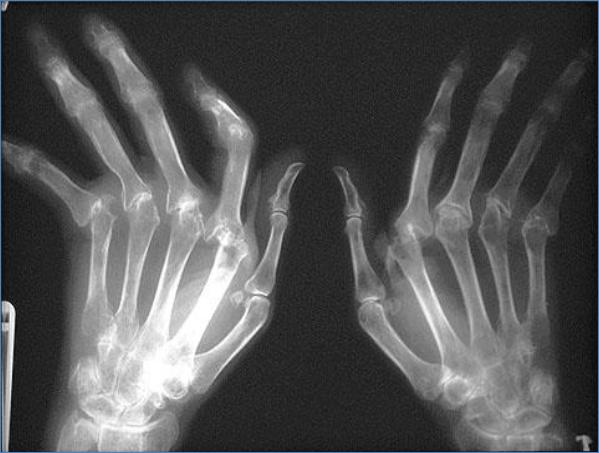

Артриты

Воспалительные изменения в суставах различной природы.

Поражение кисти при ревматоидном артрите.

Видно частичное разрушение суставных поверхностей, множественные подвывихи.